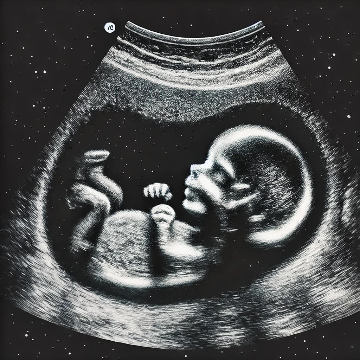

초음파 검사를 하면 임신한지 얼마 되었는지, 태아는 건강한지 언제 출산 할 수 있는지 등 다양한 정보를 알 수 있습니다.

- 초음파 검사 원리: 진단 장치의 변환기에서 자궁 속으로 음파를 보내면 음파가 태아에게 부딪쳐서 되돌아오는데, 이렇게 반사된 음파를 컴퓨터로 해석한 다음 모니터로 내보냅니다. 이 화면을 통해 태아 모습을 추정하는 것이 초음파 검사입니다. 몸에 나쁜 영향을 주지 않고 태아 모습을 여러 번 반복해서 볼 수 있기에 산과 검사의 기본으로 주로 사용하는 검사법입니다.